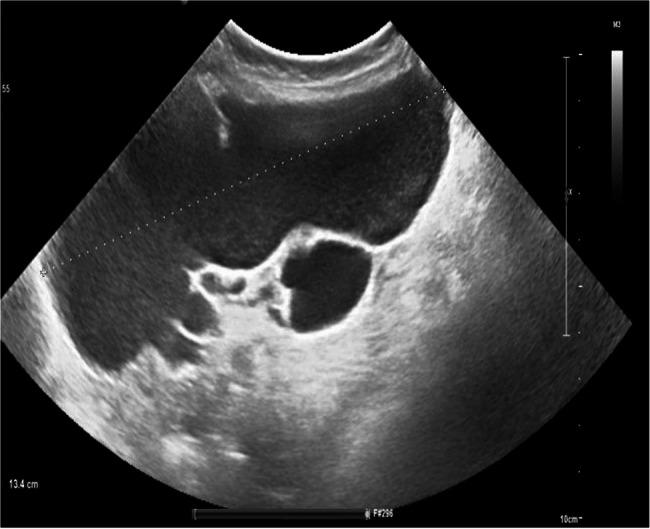

Laparoscopic management of giant abdominal cystic lymphangiomas: experience from the queen Fabiola children's university hospital.